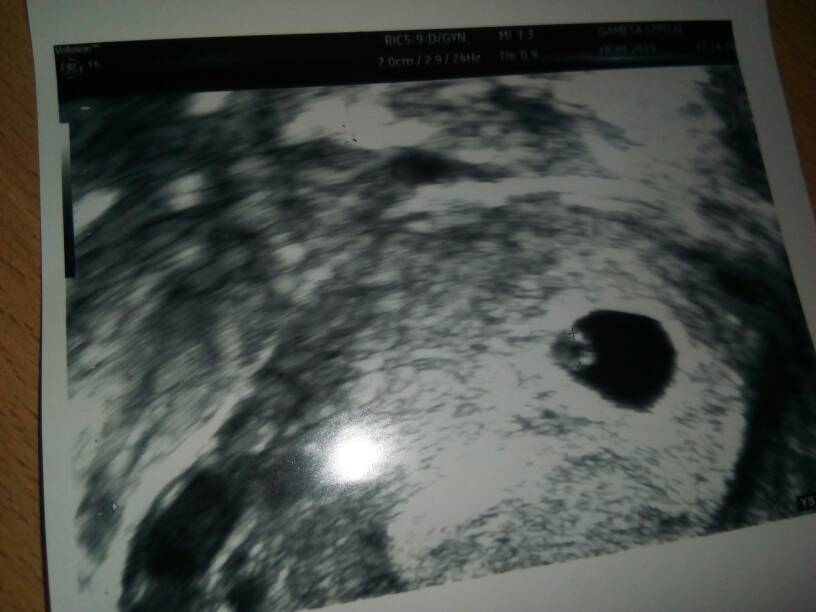

Wasze kciuki pomogły [emoji4] wczoraj wizyta 6+0, jest zarodek i to z serduszkiem [emoji175]

IMG_20190318_185612.jpeg